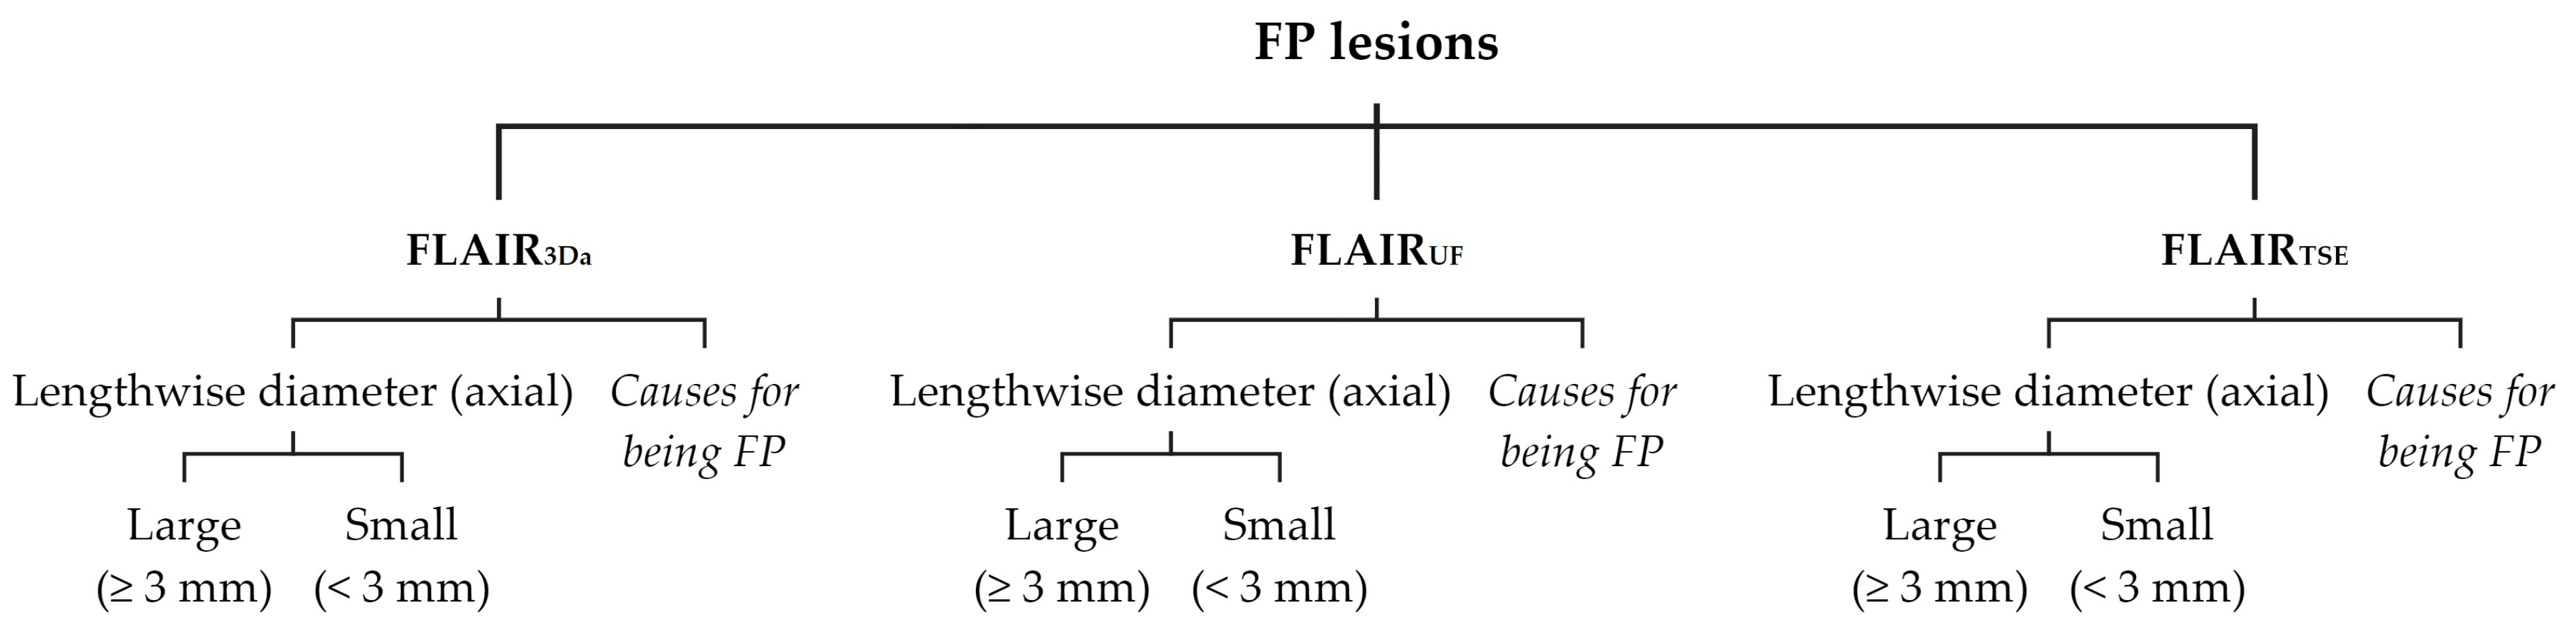

2.4.1. Lesion Assessment

3.2.1. FLAIRUF Compared with FLAIR3Da

3.2.3. Dependence on Size and Location within FLAIRUF